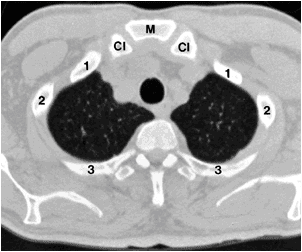

Reference:BiblioMed Textbook-Computed Body Tomography